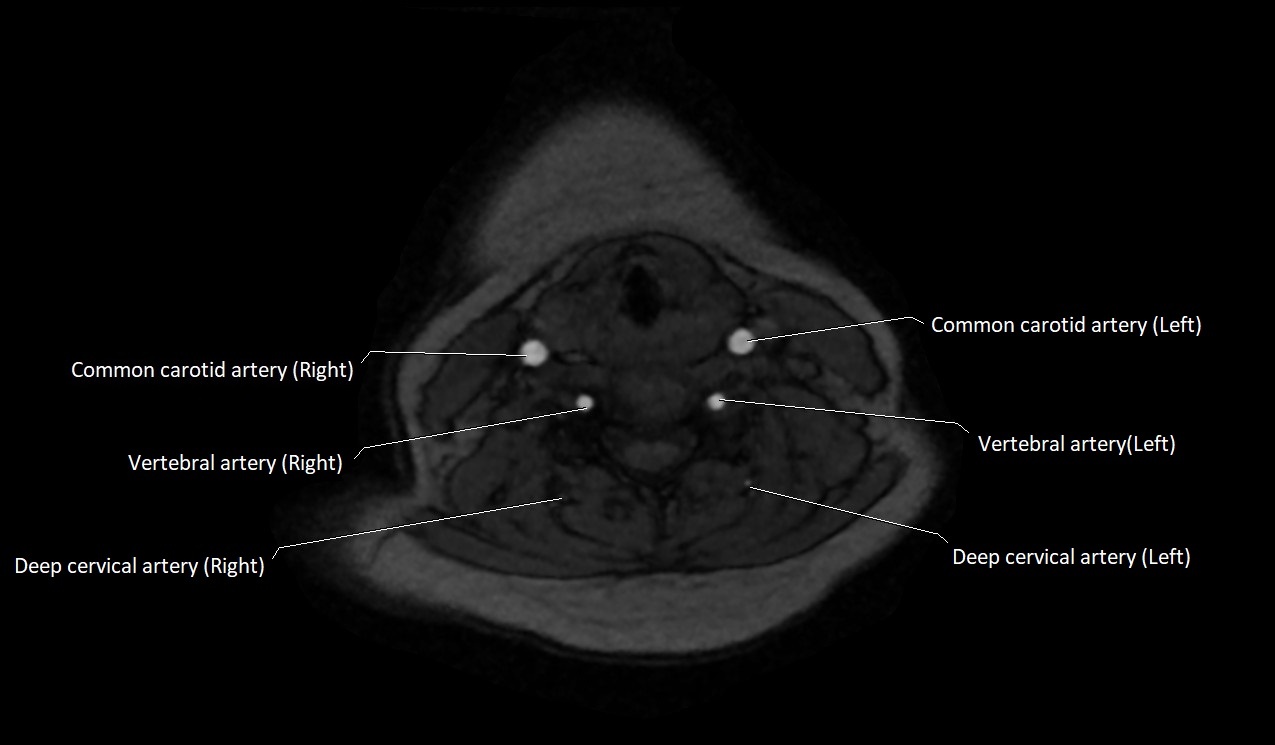

MRI Appearance:

• T1-Weighted Images:

• Appears as a tubular, hypointense (dark) structure relative to muscle

• May show flow void if the blood flow is fast

• T2-Weighted Images:

• Typically hypointense or isointense to muscle, but can be hyperintense if slow flow or stasis is present

MRI images